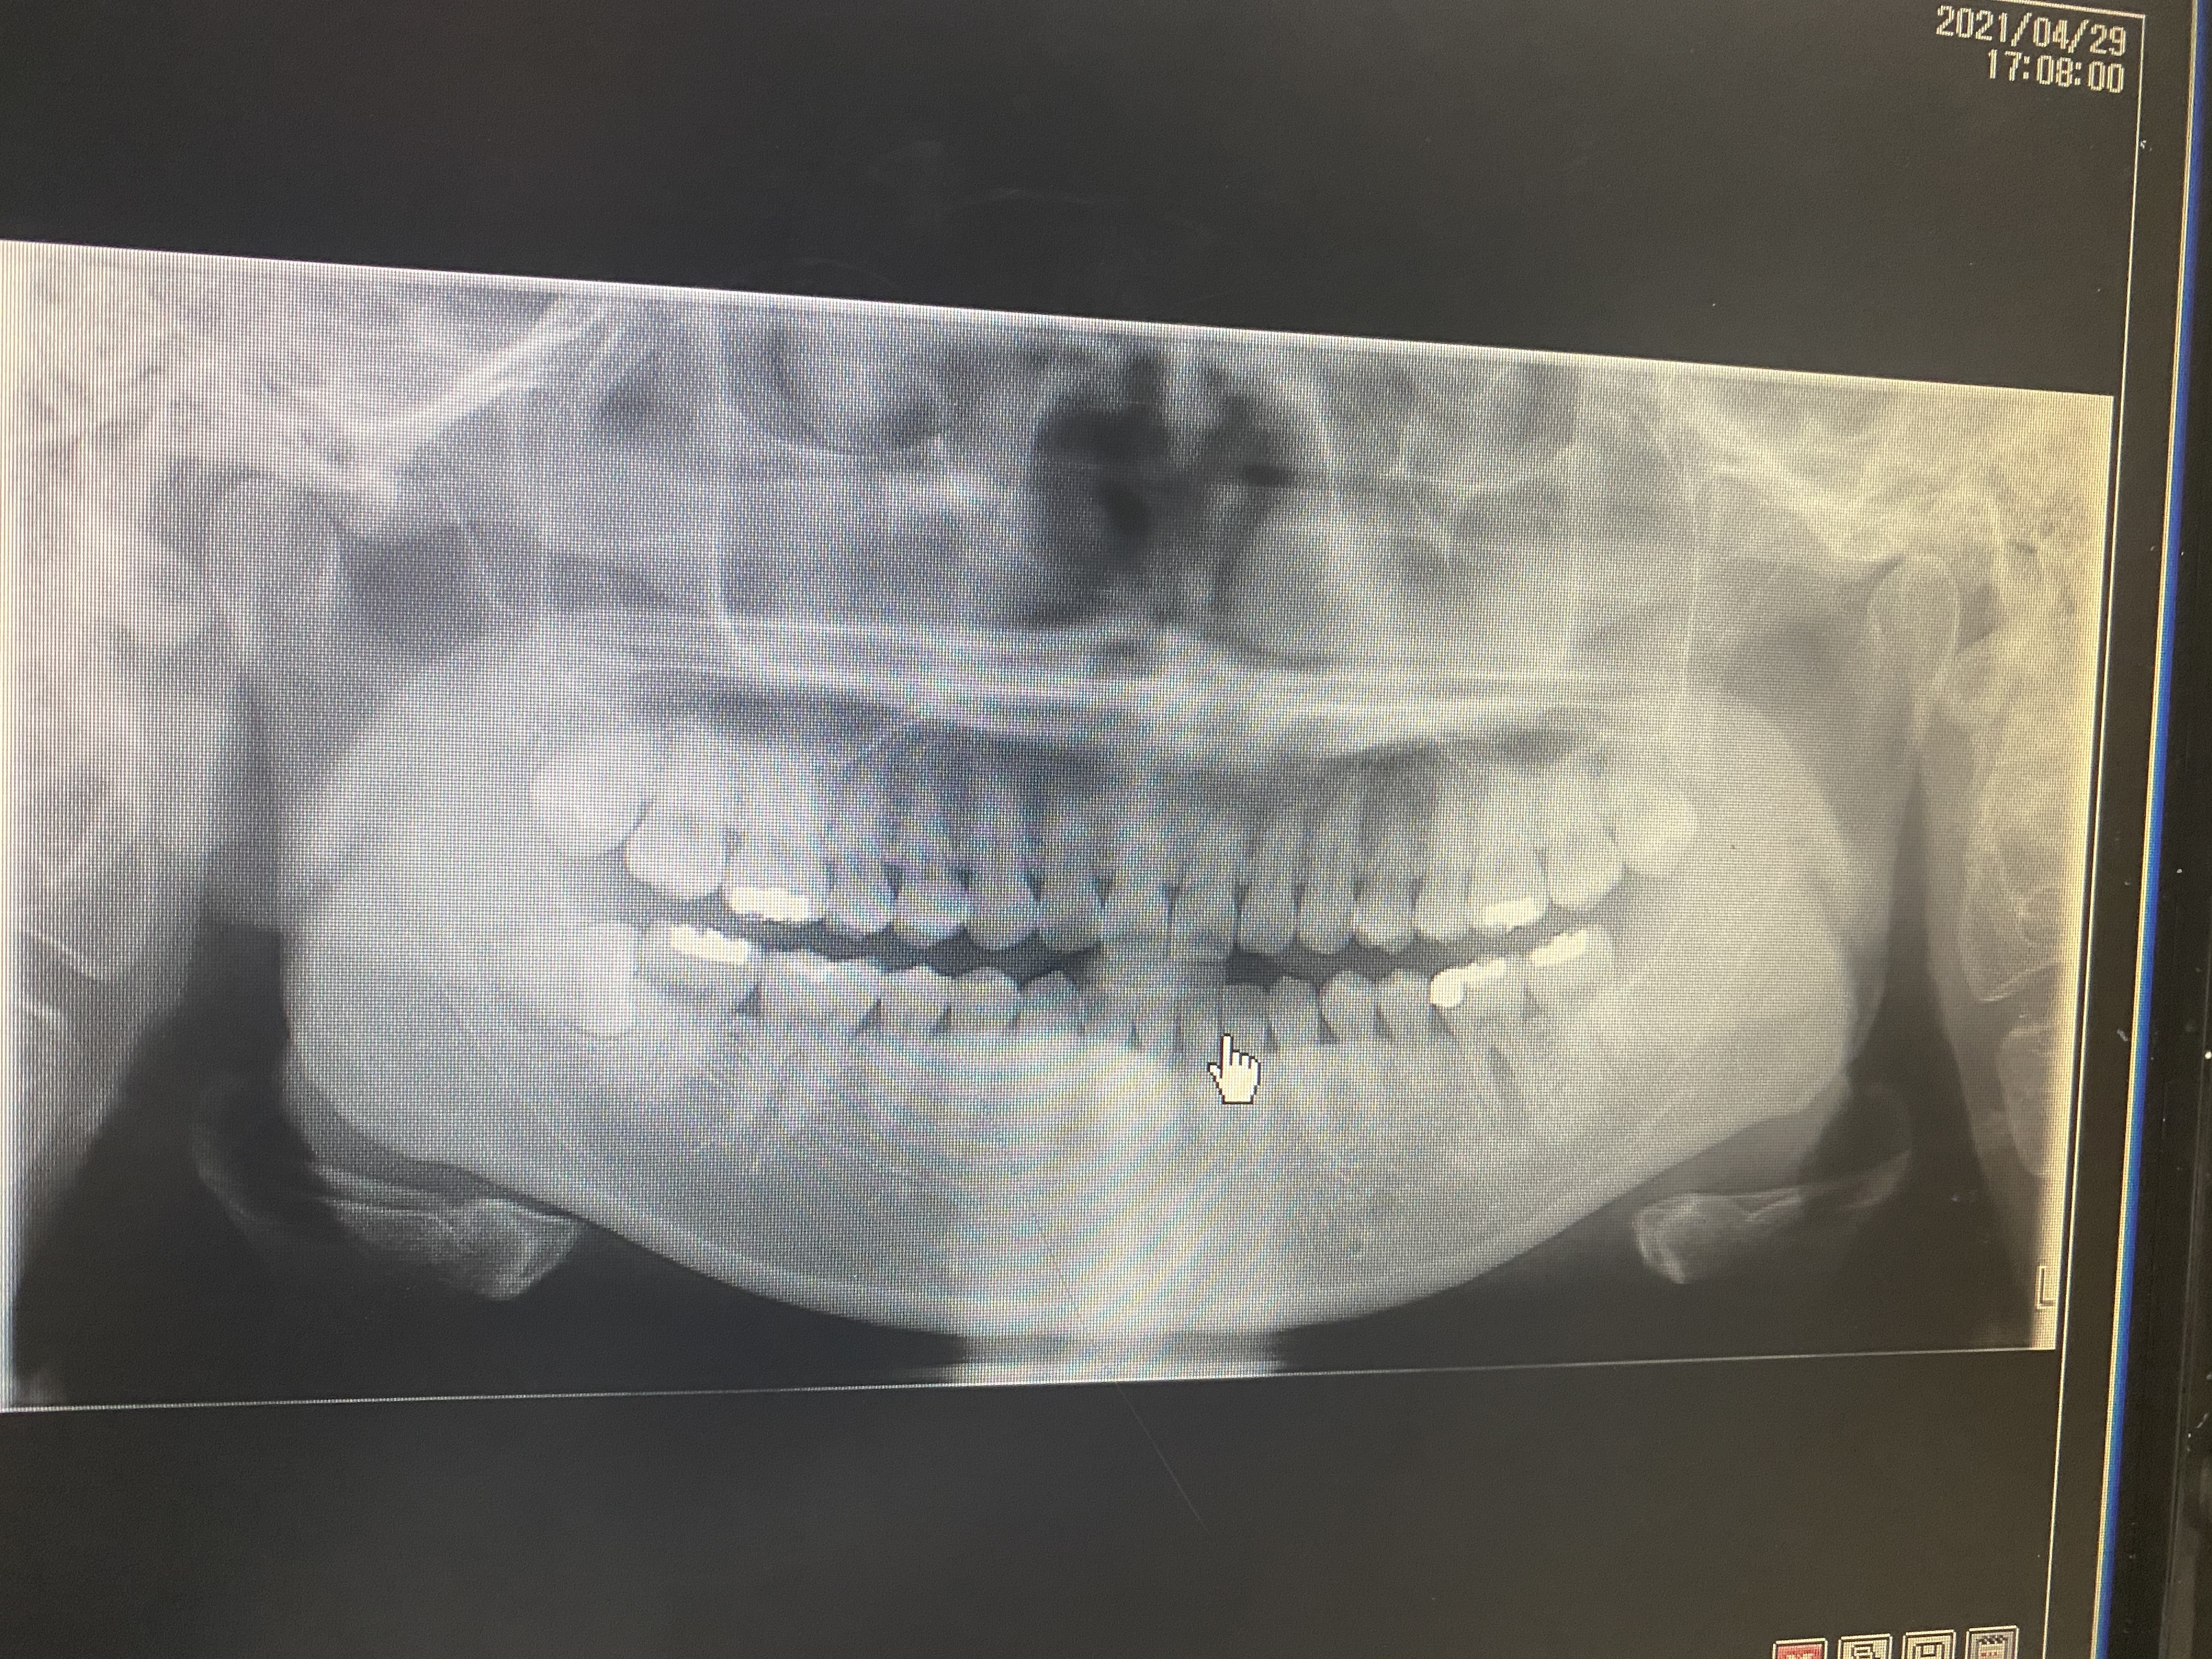

안녕하세요 선생님. 몇해전 선생님 조언으로 많은 도움을 받았었습니다. 이번에 가족이 통증이 있어 치과에 방문했는데 신경치료 또는 임플란트를 추천하더라고요. 제가보기에는 문제의 치아보면 치아부분에는 검게변하지 않아서 충치가 안보이는거 같은데 병원에서는 신경치료나 임플란트를 권하네요. 뿌리끝에도 검은 부분이 없는거 같고요. 뿌리사이에는 검게 염증이 보이는거 같습니다. 사진상으로 정확한 진단은 힘드시겠지만 조언좀 부탁드립니다. 2년전 선생님 말씀대로 신경치로안받고 저도 별다른 통증없이 잘 관리하면서 치아를 사용하고 있어서 항상 감사드립니다.

• 작성자hyuntae 작성자 본인 여부 작성자 | 작성시간 21.05.01 선생님 조언 감사드립니다. 염증이 심한건가요? 보통 검게 나오는게 염증으로 알고 있는데 사진상으로는 뿌리끝은 하얀거 같고 뿌리 사이가 검은거 같은데 그쪽이 염증이 심한건가요?